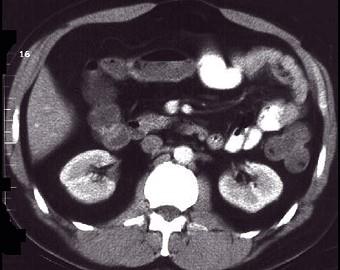

问题 女,30岁,右下腹痛,腹泻便秘交替出现,消瘦乏力,血沉加快,X线检查如图,最佳的诊断是 ( )

选项 A、结肠癌 B、阑尾炎 C、小肠结核 D、小肠克罗恩病 E、小肠癌

答案 D